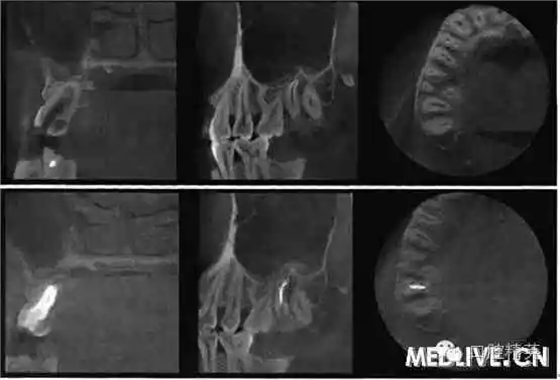

7⊥頜面中央窩見開髓洞型,叩痛(++),無松動。X線片示7⊥牙根融合為一彎曲單根,根管粗大,根尖1/3偏向遠中,無充填物,未見髓室底(圖1上)。錐形束C’r檢查示:根管橫斷面僅見一個根管口略呈啞鈴形,頰舌向管徑粗大,中下1,3存在牙本質(zhì)島,根尖1,3明顯彎曲偏向遠中,彎曲角度為34.30(圖2上)。

圖2錐形柬CT影像